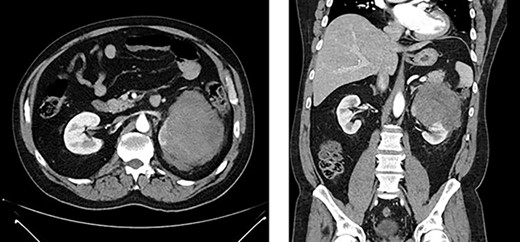

Appearance of effusion in the left retroperitoneal space in transverse (left) and coronal (right) planes on CT; it can be seen encroaching on the spleen; subsequent cytology ruled of malignant effusion.

Two weeks post-resection, the patient was recovering as expected. At 4 weeks post-resection, radiation oncology recommended 7 weeks of intensity-modulated radiation therapy to both the surgical site and at-risk nodes identified on CT. Six weeks post-resection, the patient presented to the ED with nausea and vomiting. Abdominal CT revealed a retroperitoneal effusion at the surgical site (Fig. 3). At this admission, the patient also tested positive for COVID-19, delaying drain placement and his radiation treatments for 2 weeks.